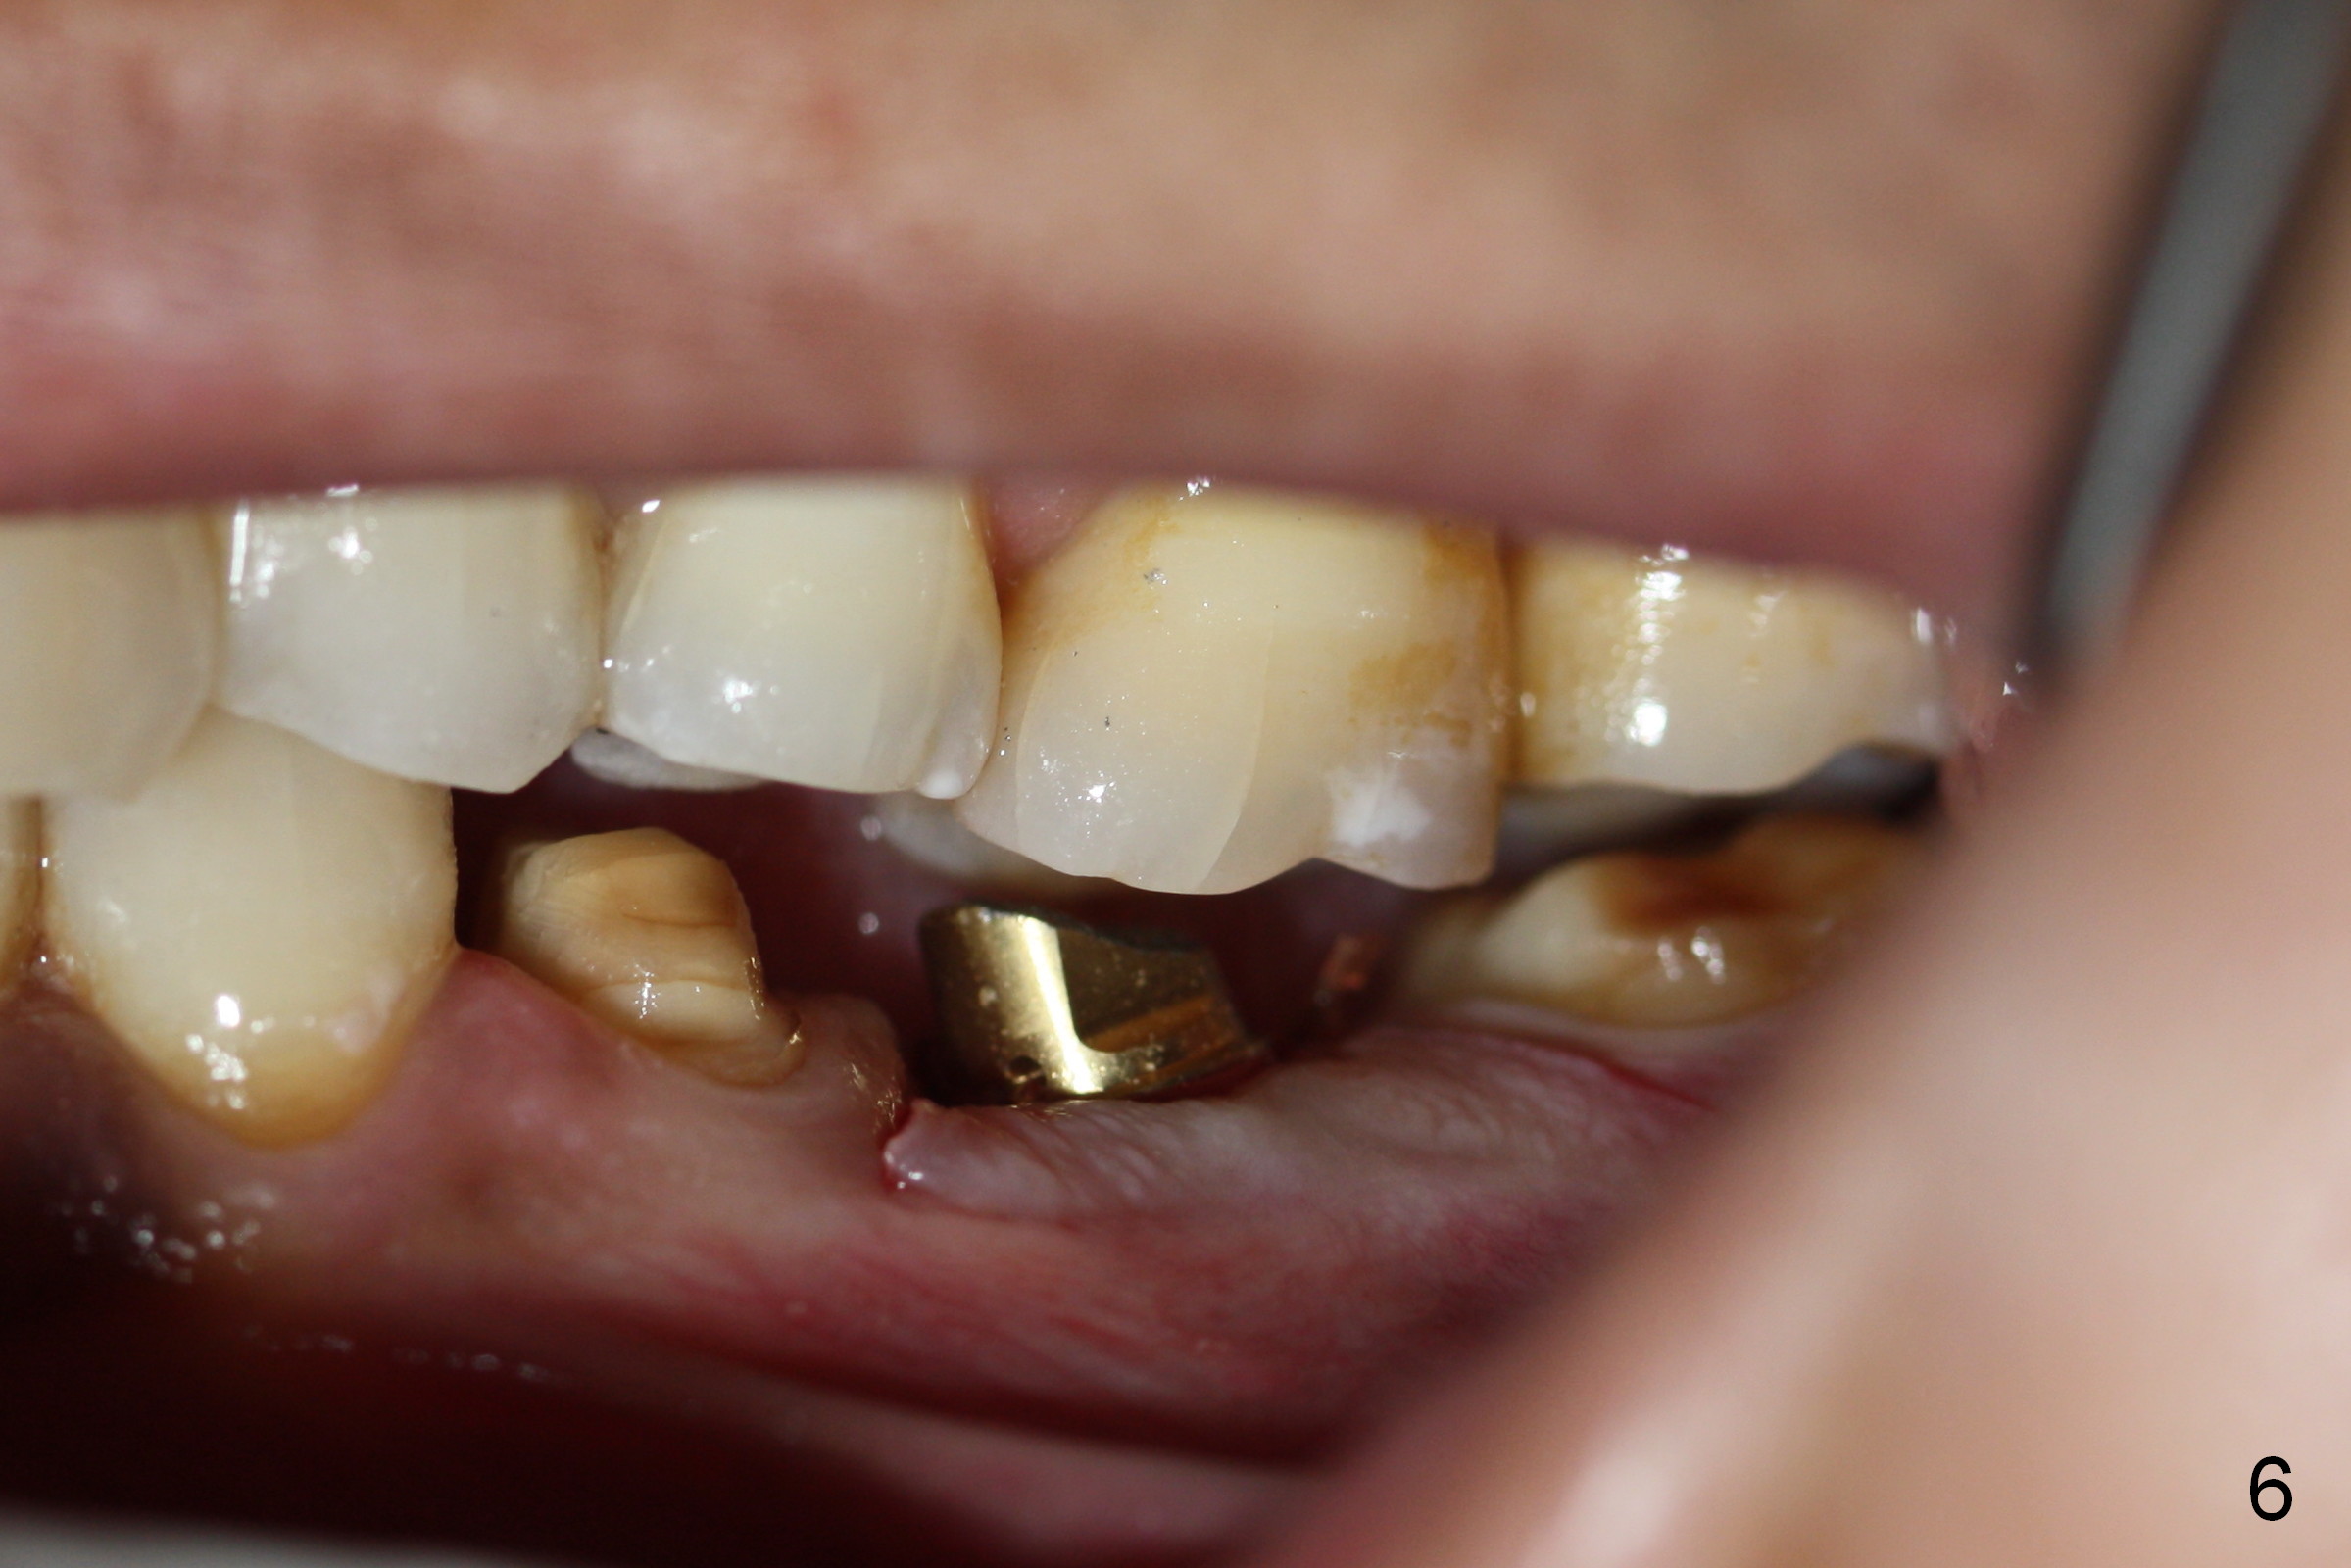

Since the implant is placed subcrestal mesially (Fig.4 >), the mesial margin of the abutment (5.8x4(3) mm) is subgingival (Fig.5 ^). An immediate provisional has to be made to keep the gingiva from growing into the margin. After occlusal clearance (Fig.6), the immediate provisional is seated (Fig.7). There is no paresthesia postop.

The patient returns for restoration 13 months postop with implant osteointegration (Fig.8) and formation of gingival cuff around the implant/abutment (Fig.9 *). In fact the immediate provisional seems to help mastication to certain degree (Fig.10). Probably it has resisted supraeruption of the opposing dentition. Impression is taken without torque of abutment screw. He smokes again.